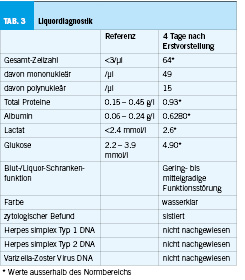

In der im Verlauf erfolgreich durchgeführten Liquoranalyse (Tabelle 2) war eine Pleozytose mit erhöhtem Proteinanteil sichtbar, bei einer leicht- bis mittelschweren Störung der Bluthirnschranke. Zweizeitig bestimmte FSME-Serologien (sowohl IgM- als auch IgG-Antikörper) fielen jeweils positiv aus (mit deutlichem Titeranstieg (Ausgangswert IgG-Antikörper: 159 U/ml; im Verlauf 1756 U/ml)), während der HSV-Typ 1/2- sowie VZV-PCR negativ ausfiel (Tabelle 3). Die empirische Therapie mit Rocephin, Aciclovir sowie Dexamethason wurde folglich gestoppt.